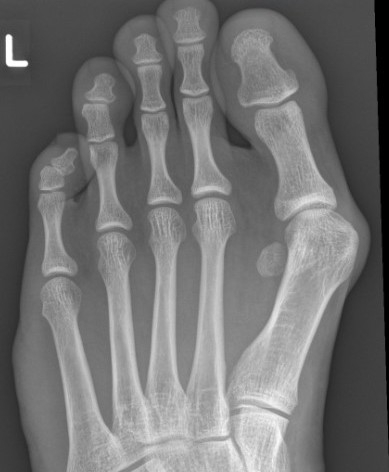

Weight Bearing AP X-ray

Angles

| HVA | DMAA | IMA | HVI |

|---|---|---|---|

|

HVA - hallux valgus angle - metatarsophalangeal angle (MTPA)

Normal < 15o |

Distal metatarsal articular angle

Intermetatarsal angle

Normal < 9o |

Hallux valgus interphalangeus

Normal <10o |

Other

| Joint congruence | Sesamoid subluxation | TMT joint obliquity |

|---|---|---|

Dots on articular surfaces - metatarsal head - base P1 |

Amount of lateral sesamoid uncovered |